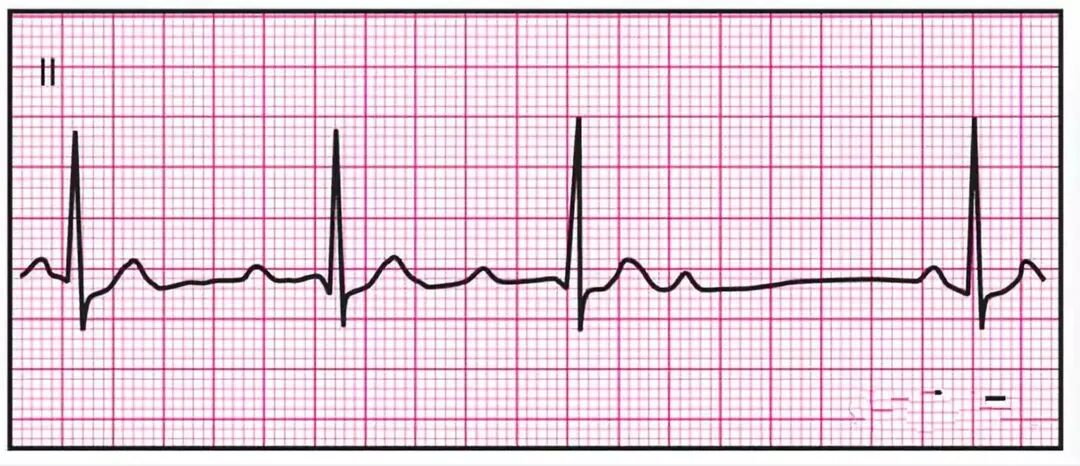

NO1、房颤

心电图特点:心房活动包括多个凹形小波,心脏收缩约为每分钟400+下 。通常显示体表心电图不规则波动(f 波),V1中最明显;P波缺失 ,室性心律完全异常,f波并一定能看到(图1),特别是当AF长期存在的情况,QRS 波群可能变宽(偏离正常位置或束支传导阻滞)。

可能由风湿性二尖瓣疾病、IHD、高血压、病态窦房结综合征、酒精、甲状腺机能亢进、房间隔缺损和特发性心房颤动引起。

图1△